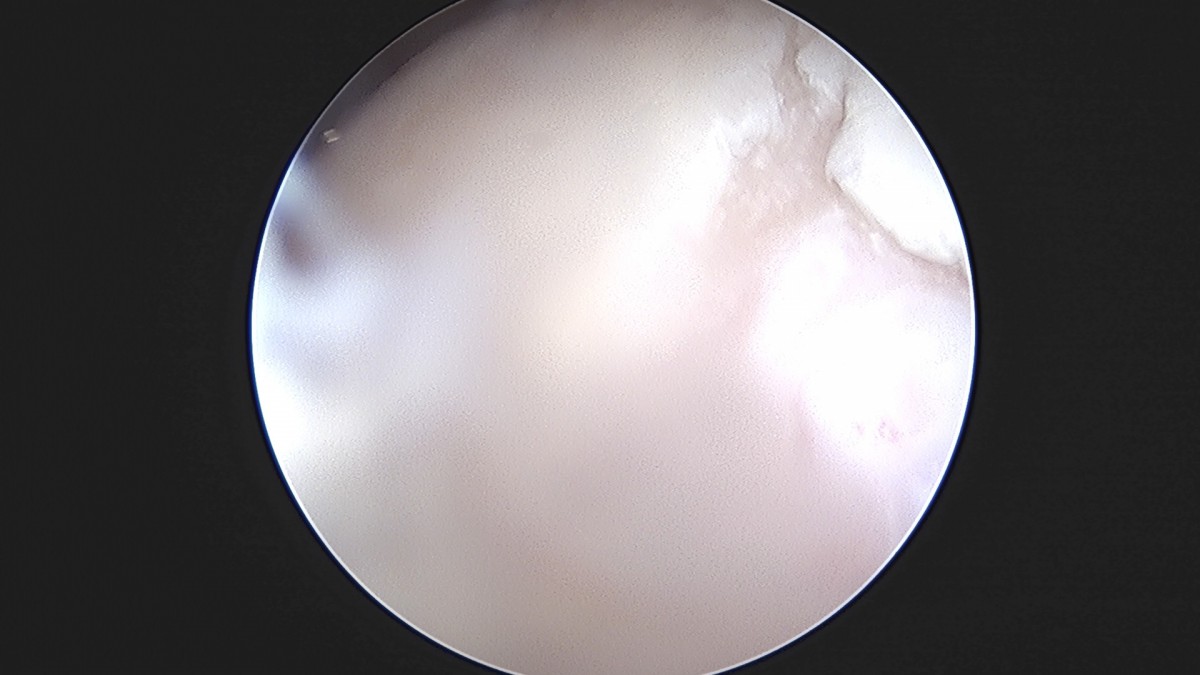

이재상원장님 무릎 반월상 연골판 절제술 최용O 환자

dae765e4d9ac96aee867c9d6292d8784_1758005820_0063.jpg